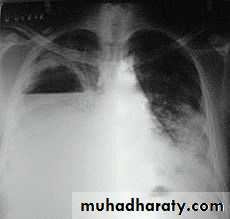

Severe dyspnea with shock